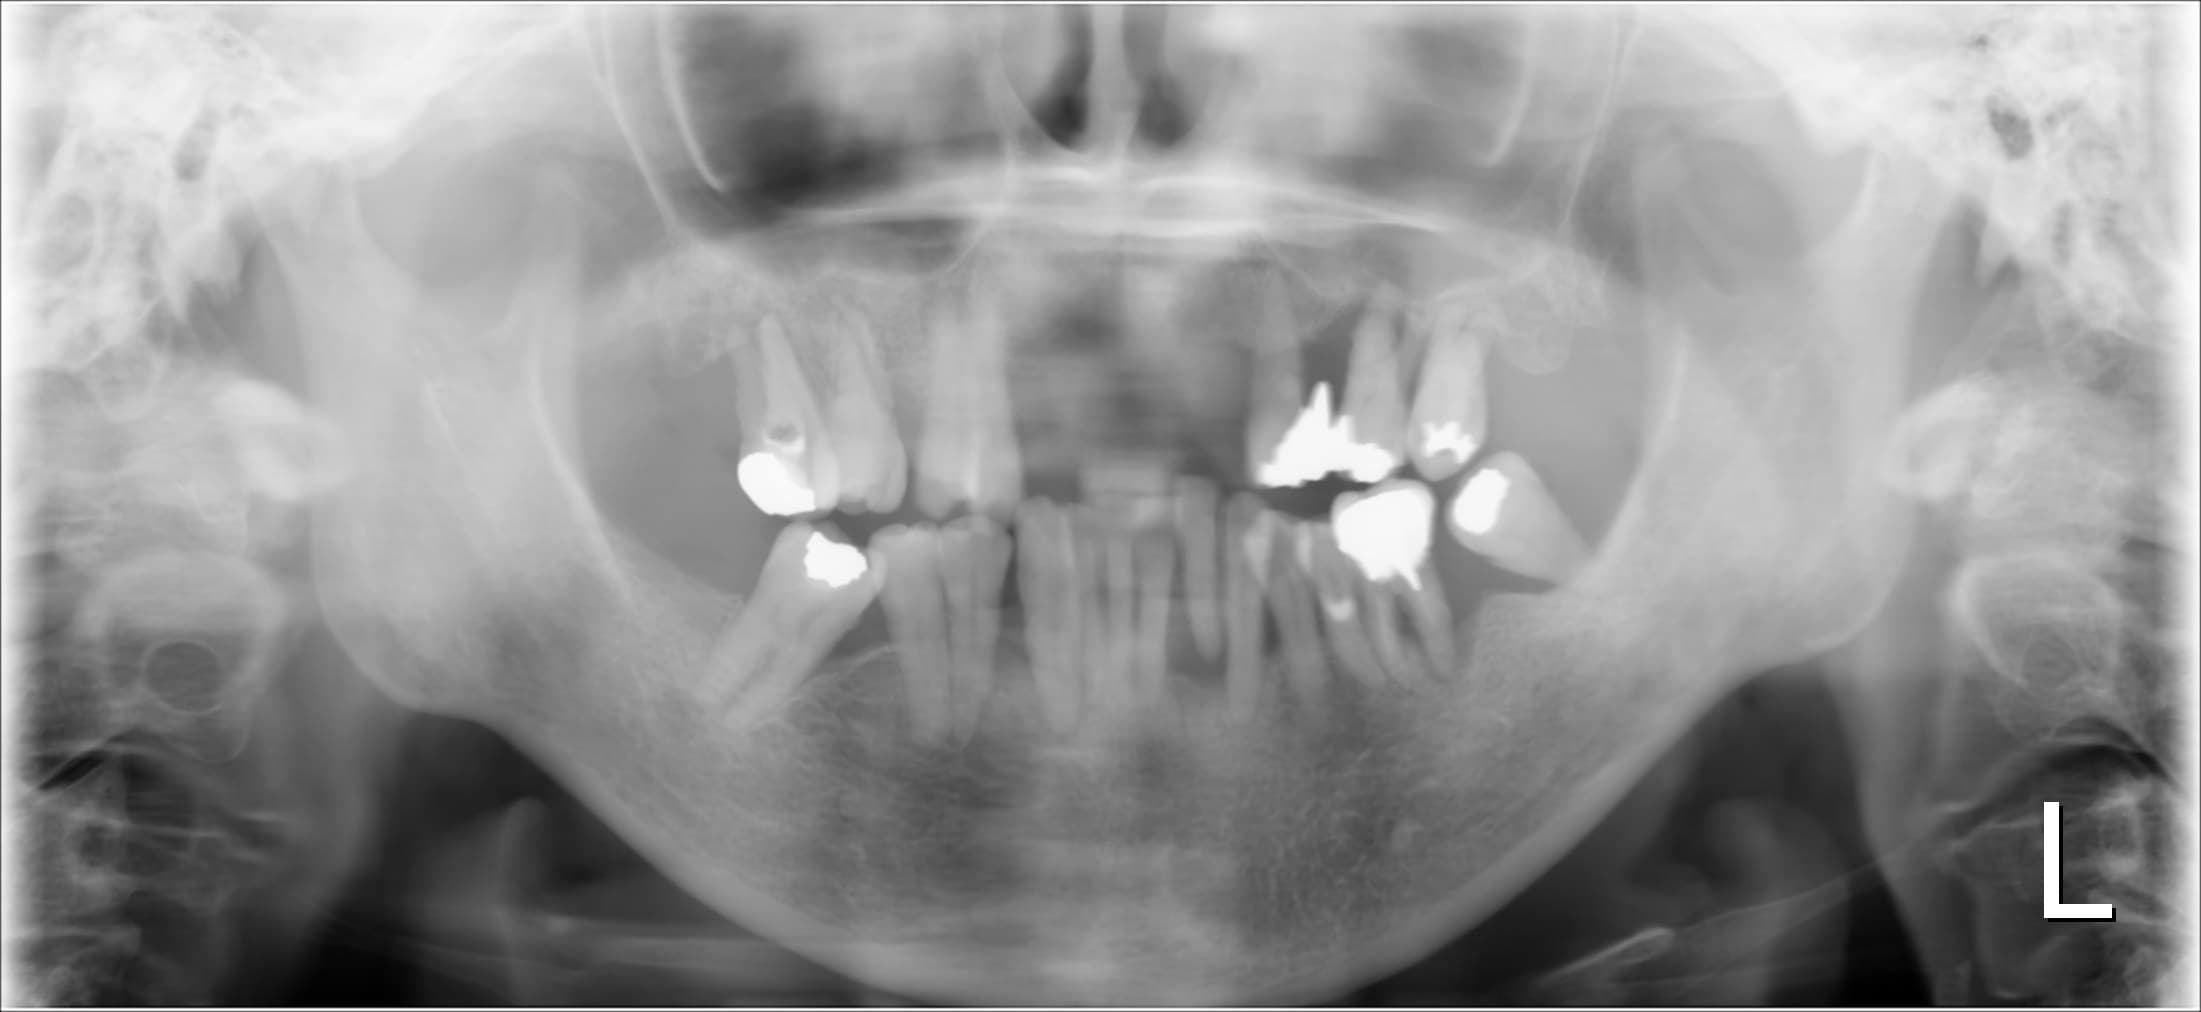

下図 当時(2009年)のレントゲン写真

当初から既に中度の歯周病があったことがわかります。